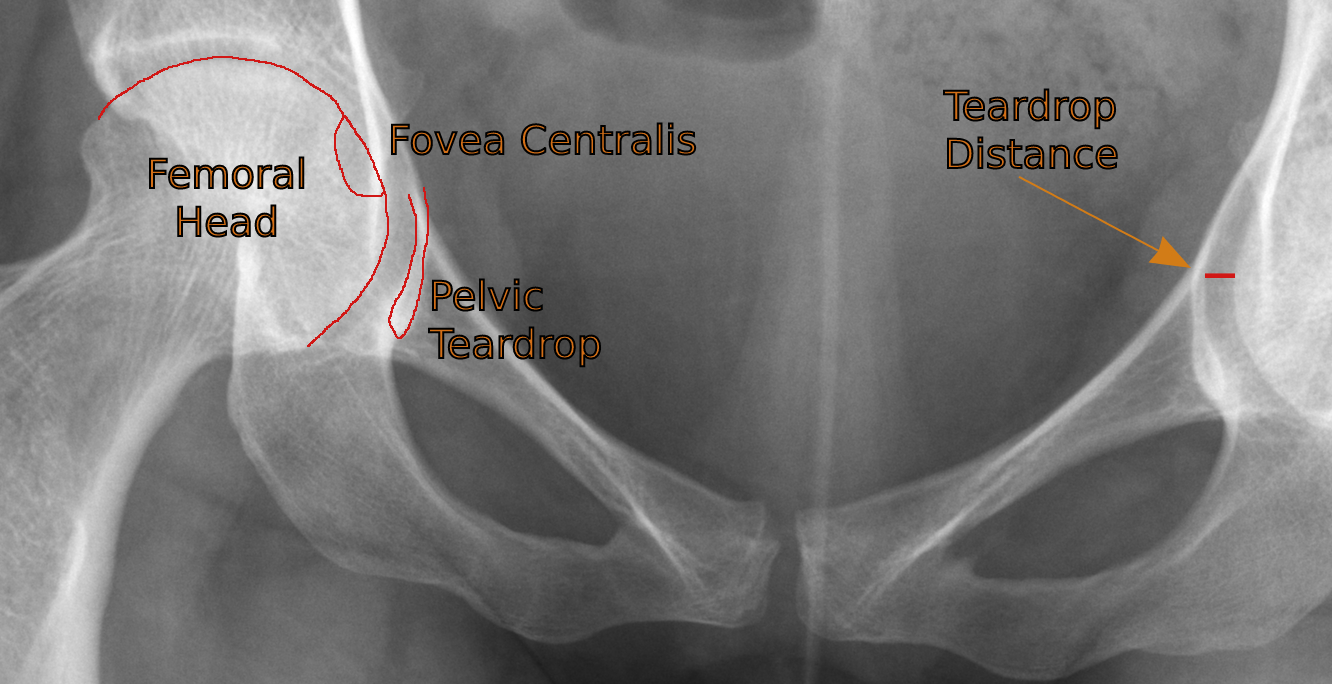

Consider the radiographic anatomy of the hip on a properly positioned, non-rotated AP pelvis -

After checking the obturator foramina for symmetry to judge whether or not the patient was rotated, we measure the teardrop distance from the most medial aspect of the femoral head to the adjacent lateral aspect of the pelvic teardrop (formed by the anteroinferior border of the acetabular fossa).

A measurement of >11mm or >2mm compared to the contralateral side is considered positive for hip joint effusion.